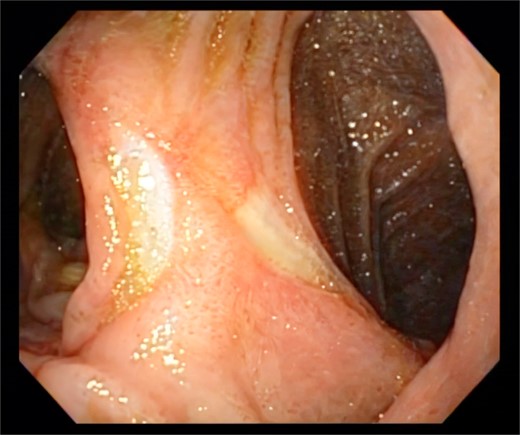

Exploratory laparoscopy revealed a large amount of intestinal fluid, fibrinous exudates, edematous intestinal loops, and a 1-cm MU at the level of the gastrojejunal anastomosis (Fig. 1). The margins were debrided and the defect was closed with absorbable poliglecaprone using a continuous suture technique. The closure was reinforced by an omental patch (Figs 2 and 3). The abdominal cavity was aspirated and irrigated. She was discharged from the hospital without complications. An endoscopy 6 months postoperatively revealed a persistent MU (Fig. 4).